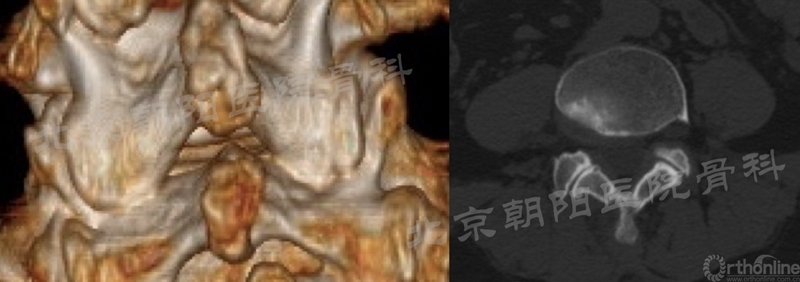

术前多看几眼三维CT,做到如下几点心中有数:

a:手术节段椎板间隙的大小和形态;

b:关节突增生程度;

c:上下椎板叠盖关系;

d:椎板厚度(指导减压工具的准备和选择)。

UBE的口号是“为狭窄而生”,但每个患者的致“窄”因素不一样,减压对象亦有所不同:

a:椎板+黄韧带+突出的椎间盘(必要时);

b-c:椎板+双侧黄韧带+双侧上关节突内聚部分;

d:椎板+黄韧带+硬膜外脂肪(重点)+硬膜表面韧带松解(谨慎)。